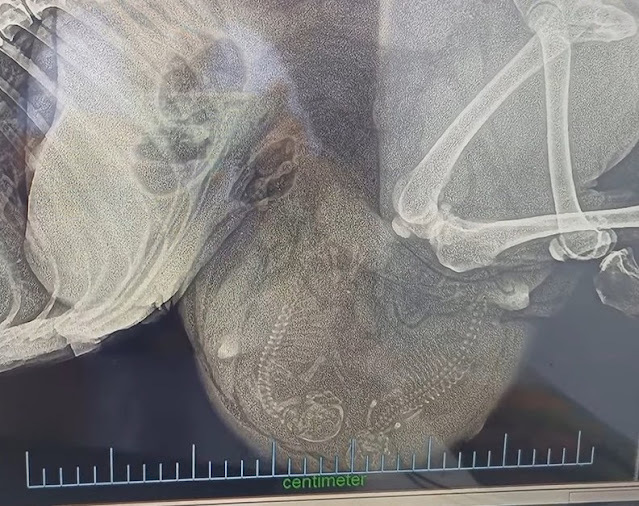

Upon her arrival, the rescue staff wasted no time in providing the care and attention she desperately needed. The mother dog was examined by a veterinarian, who conducted an ultrasound to assess the condition of her unborn puppies. The ultrasound revealed the presence of two puppies, filling the hearts of the rescuers with hope and anticipation.